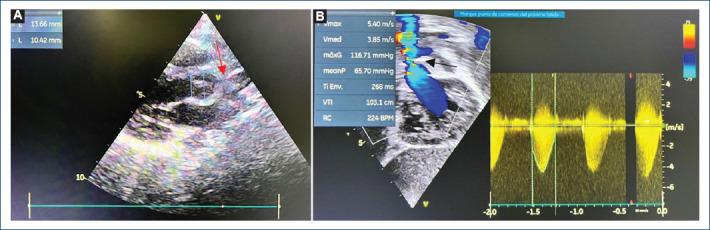

主动脉瓣上狭窄(SVAS)是一种与威廉姆斯-伯伦综合征有关的先天性畸形。其特点是窦管交界处严重狭窄。由于弹性蛋白基因的改变,平滑肌层增厚。治疗方法是外科手术,有几种缓解阻塞的技术,从单补片技术到用三个补片置换全部三个主动脉窦。然而,最佳技术仍不明确。本文旨在对 SVAS 的手术技术进行文献综述,并介绍罗伯托-吉尔伯特-埃利萨尔德医院对一名 4 岁婴儿应用 Doty 技术的情况。

Supravalvular aortic stenosis (SVAS) is a congenital malformation associated with Williams-Beuren syndrome. It is characterized by severe stenosis of the sinotubular junction. The smooth muscle layer is thickened due to an alteration of the Elastin gene. The treatment is surgical and there are several techniques to relieve obstruction which range from the single-patch technique to the replacement of all three aortic sinuses with three patches. However, the optimal technique is still unclear. The objective of this article is to carry out a bibliographic review of surgical techniques for SVAS and the description of the application of the Doty technique for a 4-year-old infant at the Roberto Gilbert Elizalde Hospital.